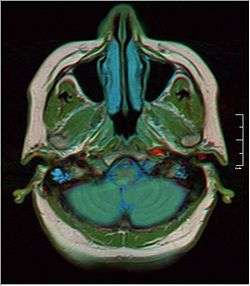

Horizontal section through left ear; upper half of section.